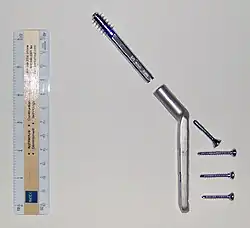

Dynamic hip screw (DHS) or Sliding Screw Fixation is a type of orthopaedic implant designed for fixation of certain types of hip fractures which allows controlled dynamic sliding of the femoral head component along the construct. It is the most commonly used implant for extracapsular fractures of the hip,[1] which are common in older osteoporotic patients. There are 3 components of a dynamic hip screw, including a lag screw (inserted into the neck of the femur), a sideplate and several cortical screws (fixated into the proximal femoral shaft). The idea behind the dynamic compression is that the femoral head component is allowed to move along one plane; since bone responds to dynamic stresses, the native femur may undergo primary healing: cells join along boundaries, resulting in a robust joint requiring no remodeling.